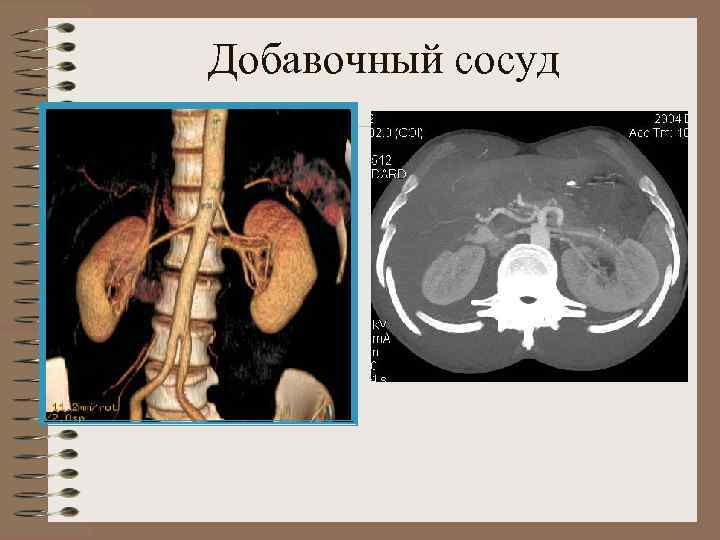

Добавочный сосуд

Добавочный сосуд. Гидронефроз

Вазоуретеральный конфликт